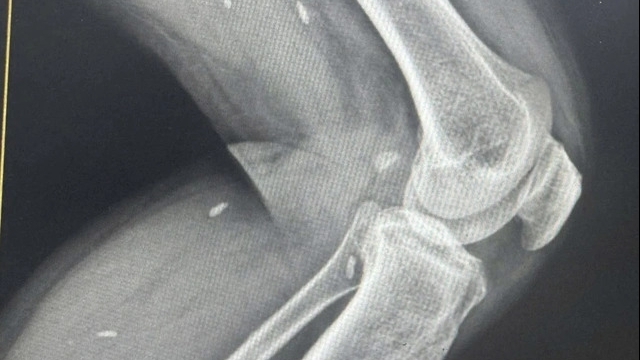

Hiện người bệnh đã được vận chuyển an toàn về Bệnh viện Quân y 175, được tiếp nhận tại Khoa Cấp cứu trong điều kiện cách ly nghiêm ngặt, triển khai các xét nghiệm, chẩn đoán hình ảnh chuyên sâu và tổ chức hội chẩn viện để xác định chẩn đoán, điều trị tích cực.